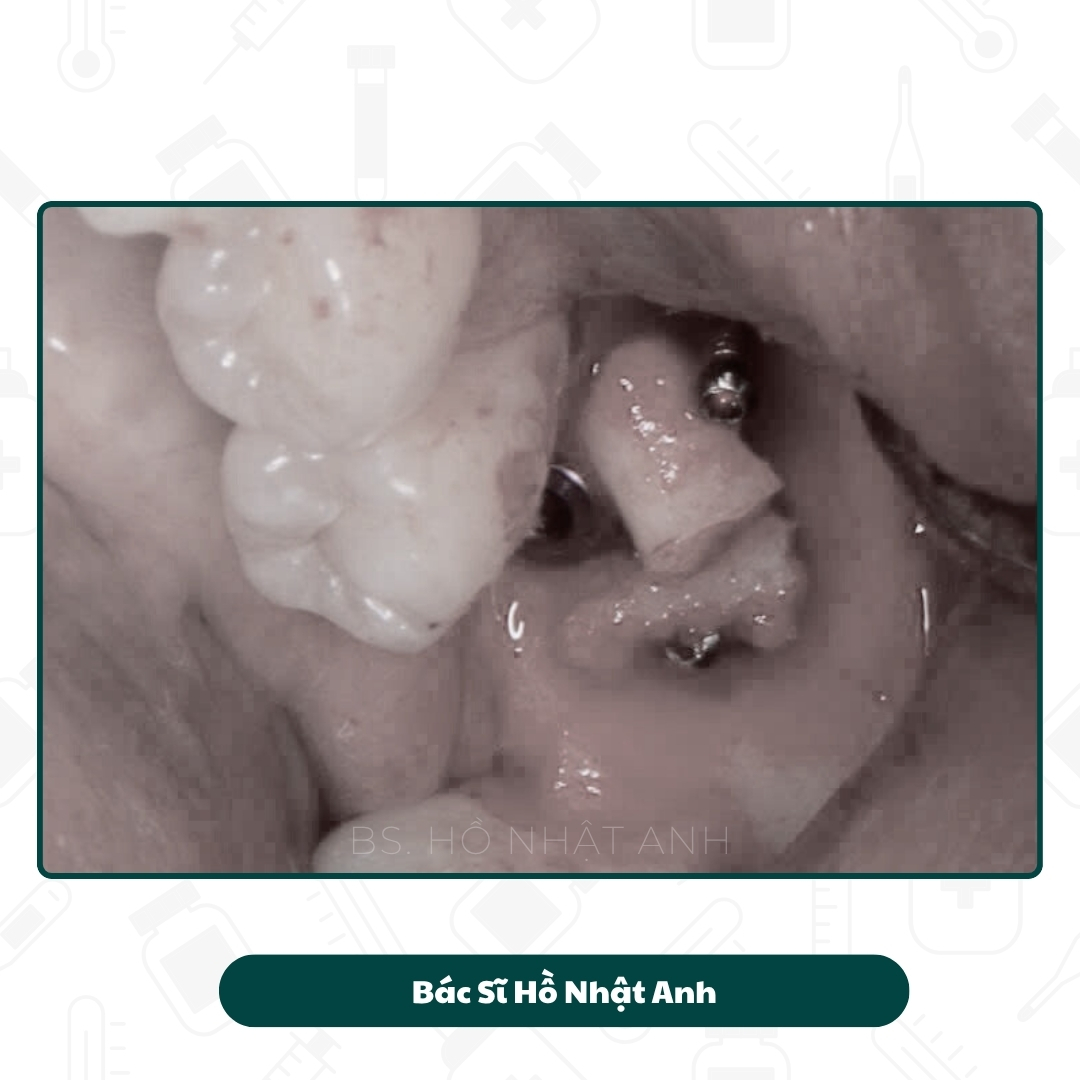

Quy Trình Cắm Implant, Ghép Xương Carotta Và Lên Răng

Quy Trình Cắm Ghép Implant

Quy trình cắm Implant, Ghép xương, xử lý mô mềm Và Lắp răng